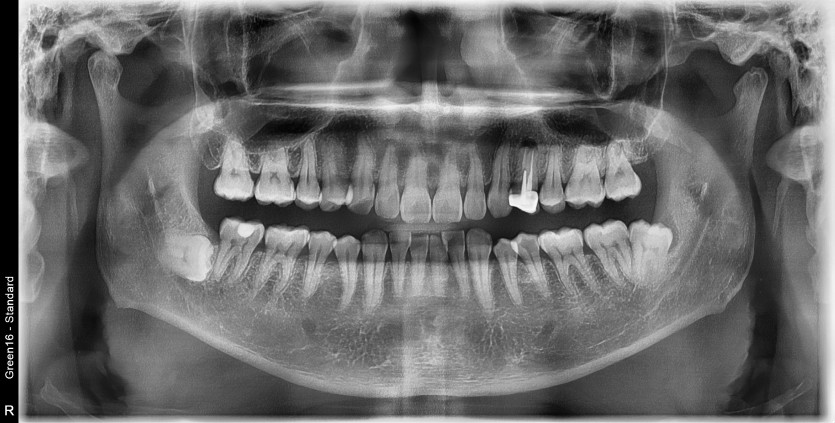

#38 사랑니 발치

구강 외과 전문의가 당일 발치했습니다.